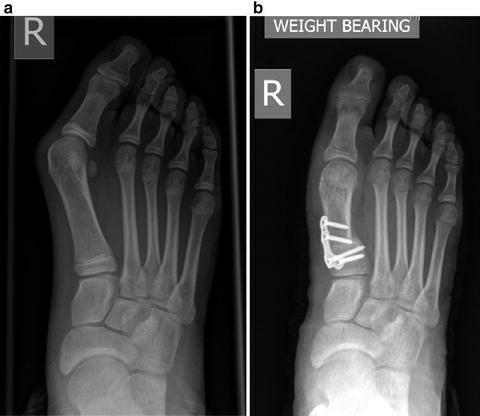

如果非手术治疗失败,可以考虑手术治疗。(证据级别:4)在选择手术前,必须确定拇外翻的严重程度。为了做到这一点,使用了负重平片射线照相术。

Lapidus关节融合术

当观察到严重的畸形时,这是另一种选择。通过切除内侧楔形关节软骨和第一跖骨基部,两者融合。用钢板或螺钉固定。

术后管理

对于所有的手术,病人可以在术后立即主管部分负重行走。患者需要矫形支具进行保护。对于年龄小于50岁和大于50岁的患者,雪佛龙截骨术后的长期随访显示同样的积极结果。